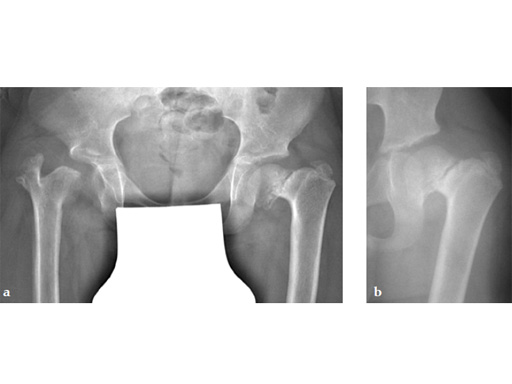

Case 2: LCP PHP 140. A 9-year-old boy, weighing 30 kg, had postinfectious pseudarthrosis of the femoral neck and varus deformity. His preoperative CC D angle was 80.

Case provided by Theddy Slongo, Bern, Switzerland